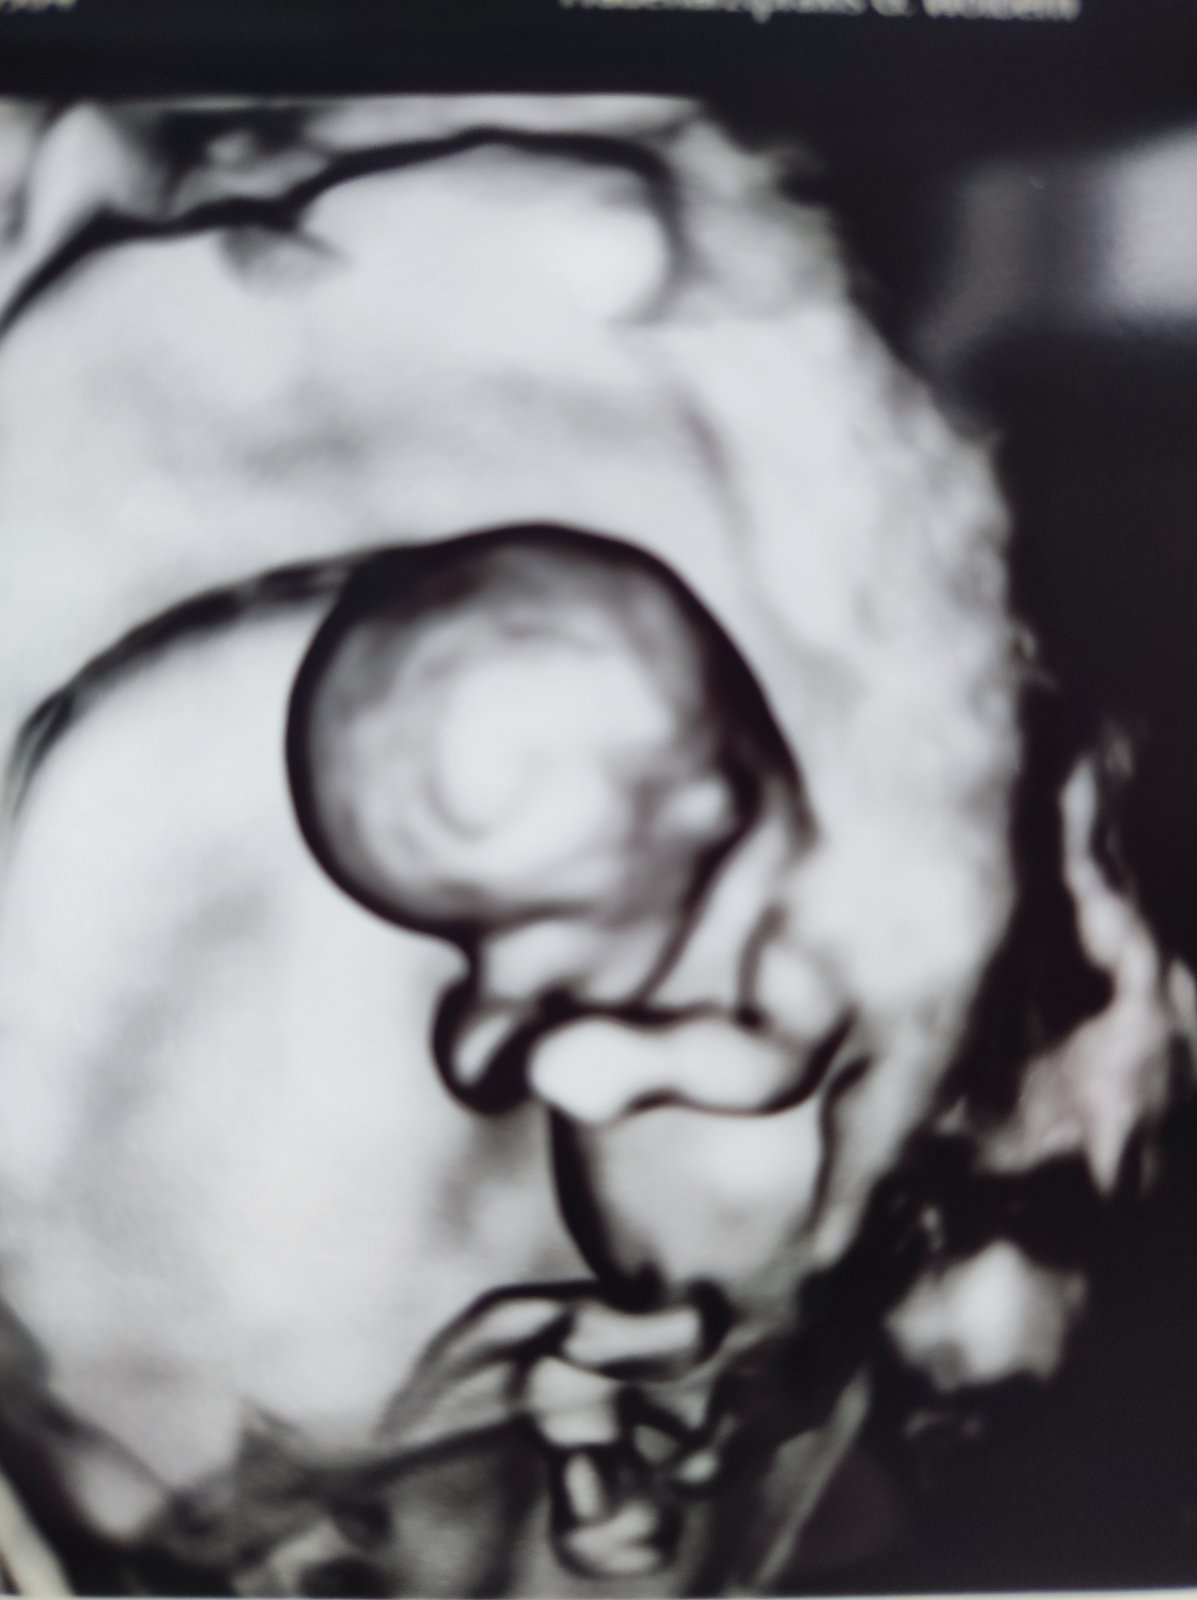

@zuza265 vsetko v absolutnom poriadku,dokonca o den vacsie🥰🥰Hybalo sa a suchalo si ocka a srdiecko krasne bilo👌👌4cm a mame tehotensku knizku🥰

@adulka25 nevedia,dnes sa hadaju ako kone ani neviem kvoli comu,chcem im to povedat v klude...jeden den hore dole...v stredu o tyzden idem na ten velky ultrazvuk + krv na Genetiku.